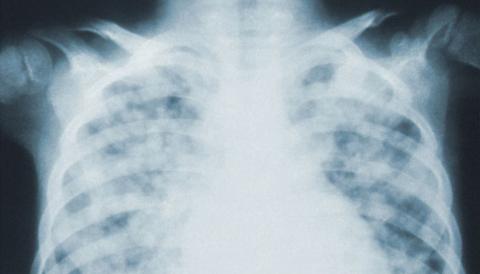

The researchers found that a pre-trained neural network called DarkNet-19 can rapidly and reliably detect COVID-19 on chest X-rays. The network recognized the disease’s imaging patterns on nearly 6,000 chest X-rays with 94 per cent accuracy, outperforming 16 other available networks.

X-rays typically take about five minutes to complete and five minutes to interpret, but the artificial intelligence-enhanced method can provide a "COVID-19 score" — the probability that a patient has the virus — within one minute.

“In the earliest stages of COVID-19, chest X-rays often appear normal to the naked eye,” says Savvas Nicolaou, the senior author of the study and the director of emergency and trauma imaging at Vancouver General Hospital. “But in the right clinical context, applying AI-augmented analysis to the same images may reveal the subtle presence of the disease.”